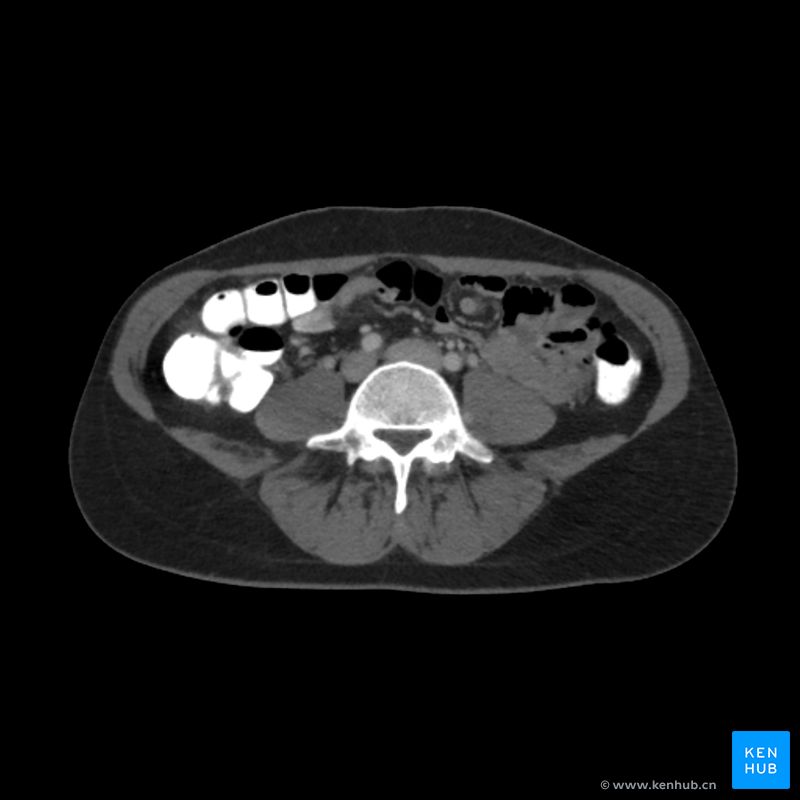

腹部CT读片入门

这篇文章将结合具体的腹部CT图像实例,向你详细介绍如何解读腹部CT影像。

腹部CT

在介绍腹部CT中可见的结构之前,我们首先需要了解腹部CT观察人体的方向。临床上最常用的扫描方向是轴位扫描,产生的图像为横断面图像。不过,如果有需要,CT也也可以生成其他方向(如冠状位或矢状位)的图像。当阅读轴位扫描的CT影像时,我们可以想象自己从患者的脚部向头部看去,因此观察到图像的左侧实际对应着患者的右侧。

CT检查的结果中会包含一系列的横断面扫描图像。这些图像可以进一步组合成三维图像(三维重建)。此外,CT扫描还可通过调节窗宽和窗位来调整图像的对比度,以突出特定的组织结构。在腹部CT中,医生通常会根据需要在“骨窗”和“软组织窗”之间进行切换。为了完整观察腹部的各解剖结构,检查者需要自上而下,从头端向尾端逐层依次查看图像切片。

使用CT检查腹部情况时,应使用系统性的方法进行评估,即逐个器官、逐个结构地详细观察。当患者因特定的临床问题(如骨折)进行CT检查时,放射科医生阅片时不能只关注某一特定结构,而应仔细评估整个扫描范围,避免遗漏其他结构的微小病变。推荐的腹部CT系统性阅片步骤包括: